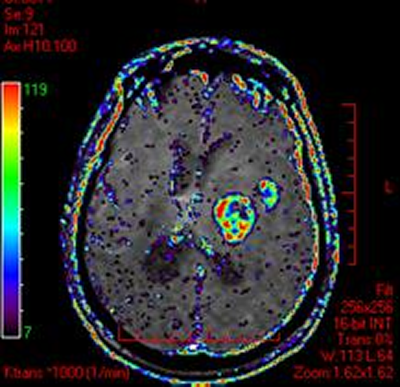

DCE-MRI permeability map color overlay on MRI in cervical cancer (left) and brain tumor (right). Data courtesy of Dr Nick Ferris, Peter MacCallum Cancer Center, Australia.